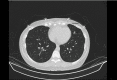

Figure 2

Figure 2. Computerized tomography of the chest in 2021 showing an increase in the lung nodule size to 15 mm